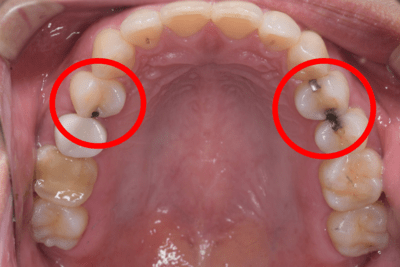

アマルガムの見分け方

・アマルガムは銀色の詰め物です

・時間が経つと酸化して黒ずみます

・30年以上前に治療したものであれば、アマルガムである可能性があります

自分で判断することは難しいので歯医者さんでレントゲンを撮って診てもらいましょう。